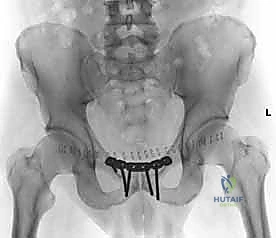

بمجرد استعادة الوضع الصحيح للعظام، يقوم الدكتور هطيف بتثبيتها باستخدام صفيحة معدنية متخصصة (غالباً صفيحة إعادة بناء متعددة الثقوب مصنوعة من التيتانيوم أو الفولاذ المقاوم للصدأ الطبي). يتم تثبيت هذه الصفيحة عبر المفصل العاني باستخدام مسامير قشرية (Cortical Screws) تُغرس بعمق في عظام العانة الصلبة لضمان تثبيت قوي يتحمل ضغط الجسم.

بعد التأكد من قوة التثبيت من خلال الأشعة السينية داخل غرفة العمليات (Fluoroscopy)، يتم إغلاق الجرح على طبقات باستخدام خيوط جراحية تجميلية قابلة للامتصاص، مع وضع أنبوب تصريف (درنقة) لمنع تجمع السوائل.